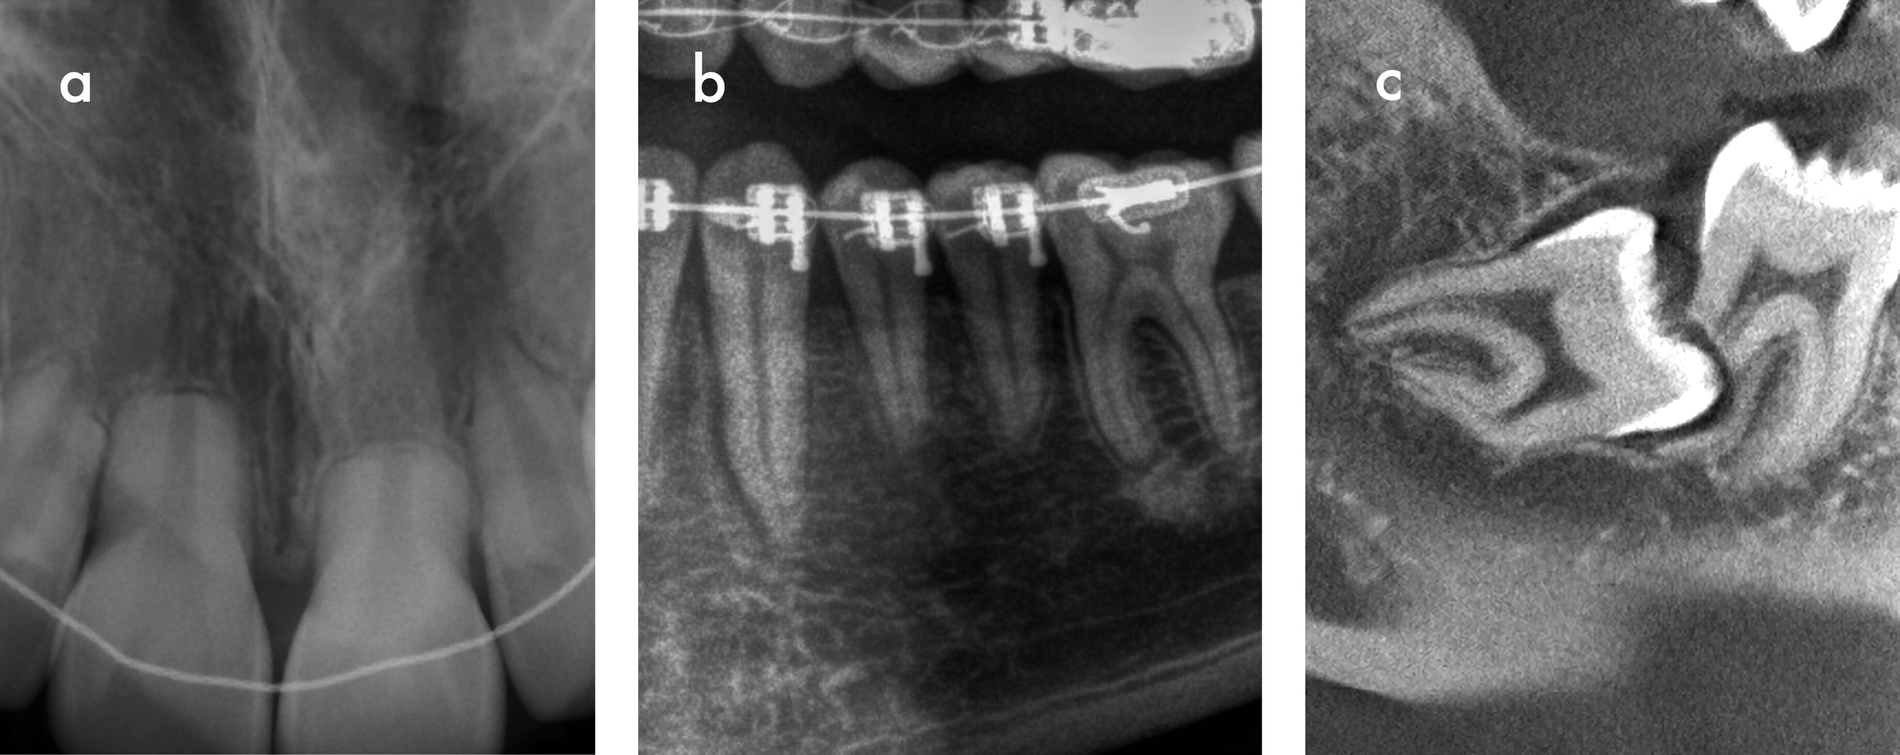

Der klinische Verlauf von externen Oberflächenresorptionen ist in der Regel asymptomatisch und die betroffenen Zähne reagieren meist positiv auf Sensibilitätstests. Die radiologischen Befunde sind in Form und Größe sehr heterogen (Abbildung 5). Im Zusammenhang mit kieferorthopädisch bedingten Resorptionen ist beispielsweise häufig eine scheinbare Abstumpfung der Wurzelspitze zu beobachten, wodurch die Zähne insgesamt kürzer erscheinen als die nicht von resorptiven Prozessen betroffenen Nachbarzähne [Sameshima und Iglesias-Linares, 2021; Sondeijker et al., 2019].

Dabei wird das Dentin zunehmend durch Odontoklasten abgebaut und durch Knochengewebe ersetzt [Andreasen, 1980; Souza et al., 2020]. Die daraus resultierende Verschmelzung von Zahn und Alveolarknochen wird als Ankylose bezeichnet und äußert sich klinisch durch ein helles, metallisches Klopfgeräusch und das Fehlen der physiologischen Zahnbeweglichkeit (Abbildung 8). Im Laufe der Gebissentwicklung kann es als Folge der Ankylose zu Infrapositionen der betroffenen Zähne kommen. Der Parodontalspalt ist röntgenologisch nicht mehr eindeutig erkennbar [Andersson et al., 1984].